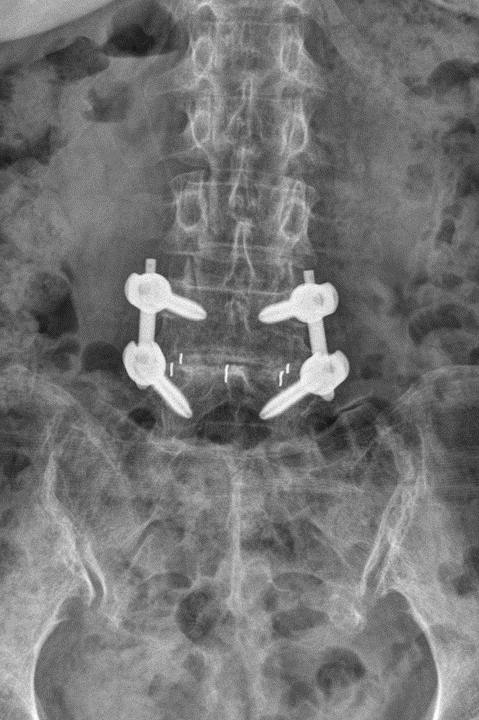

척추 안정성 복원: 요추 척추체간 유합술은 척추경 나사 고정을 통해 척추를 안정화하고 변형을 교정하며 추가 퇴행성 변화가 발생하지 않도록 해 재발을 현저히 줄일 수 있습니다.